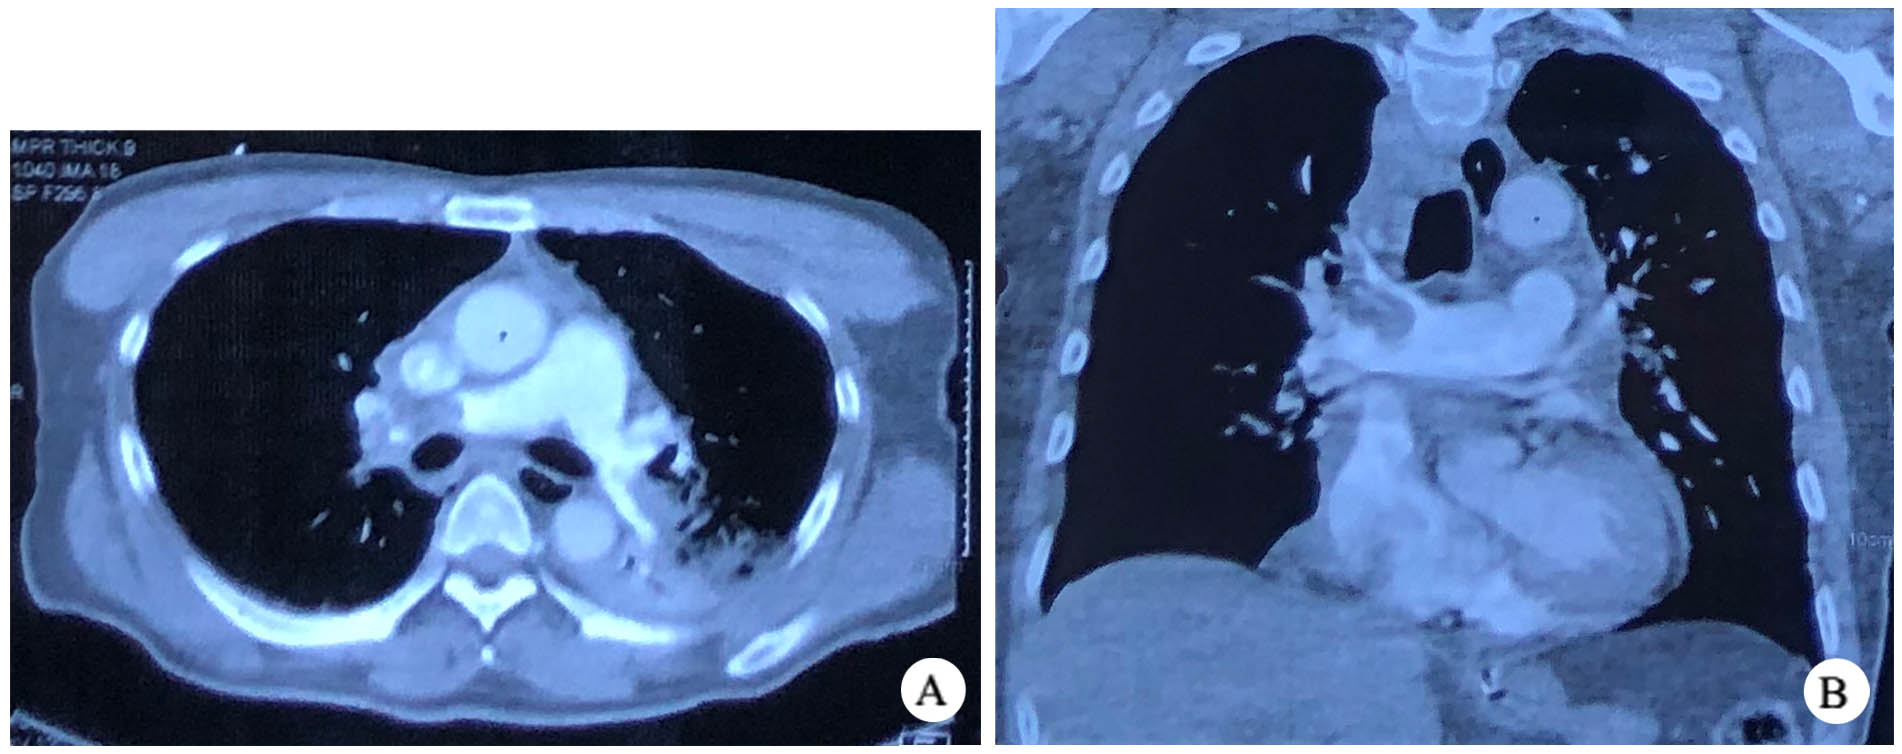

患者,男性,64岁,因“意识不清8 h”于2022年12月5日转入本院急诊。患者8 h前被路人发现意识不清、倒卧在地,路人报警后2 min交警赶到现场,发现患者心脏骤停,立即开始心肺复苏并呼叫120。120到达后进行气管插管并心肺复苏,院前复苏共22 min。送达邻近医院后继续复苏7 min,患者恢复自主心律,行CT肺动脉造影示右肺动脉主干栓塞(图 1)。

| A:横断位; B:冠状位 图 1 术前CTPA显示右肺动脉栓塞 |